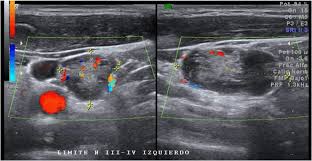

Head and neck cancers include cancers in: There can be more than one sentinel node. I had an ultrasound done in 2012 but the report for this scan never reached my previous doctor's practice and so nothing was. This study was done to evaluate the use of ultrasound to examine lymph nodes in the neck in surgical planning for thyroid cancer surgery and to identify which patients are best served. An ultrasound of the thyroid produces pictures of the thyroid gland and the adjacent structures in the neck. While it can't diagnose cancer, it can detect the abnormal tissues that may possibly be cancerous. The image may or may not suggest cancer, but definitive diagnosis requires removal of. For most types of cancer, a biopsy is the only sure way for the doctor to know if an area of the body has cancer. When ultrasound is performed on a patient with nodular goiter, or a patient with a history of thyroid cancer, finding a prominent lymph node with a rounded shape (long/short axis ratio < 2) and absent hilar line warrants further evaluation of the node (figs. Ultrasounds have many limitations an ultrasound is not good enough for many aspects of cancer. Carotid ultrasound tests for blocked or narrowed carotid arteries, which can increase the. Confirming that a lump in the neck is developing from the thyroid or connected tissue. Spread of thyroid cancer to the lymph nodes in the neck is common and increases the risk of cancer recurrence.

Figure 3 From Post Thyroidectomy Neck Ultrasonography In Patients With Thyroid Cancer And A Review Of The Literature Semantic Scholar from d3i71xaburhd42.cloudfront.net Ultrasound is often one of the first line tests in the detection of cancer. These tests can also show whether a nodule is toxic or producing too much thyroxine, causing hyperthyroidism. Spread of thyroid cancer to the lymph nodes in the neck is common and increases the risk of cancer recurrence. I was officially diagnosed hashimoto's by my endocrinologist 2 weeks ago but she has refused to do an ultrasound of the thyroid. 8.4, 8.5, 8.6, 8.7, and 8.8). An ultrasound of the neck is used to examine the carotid arteries located on each side of a patient's neck. Our doctors also use ultrasound to check lymph nodes in the neck, where some forms of thyroid cancer can spread. It can be used with a fine needle aspiration test or core biopsy test to accurately direct the tip of the needle into the lump.

Carotid ultrasound tests for blocked or narrowed carotid arteries, which can increase the. Some of the indications for thyroid or neck ultrasound are thyroid nodules, goiter, thyroid cancer and other neck masses. Expert ultrasound can also help confirm a diagnosis of papillary thyroid cancer which has spread to the lymph nodes of the neck. It can detect abnormal tissues, growths, and cysts and give a suspicion of cancer based on how those images look. Ultrasound is widely available an is useful to identify abnormal lymph nodes that may contain cancer.

People may use the word throat to describe different parts of the neck. Your two carotid arteries are located on each side of your neck. A neck ultrasound can be used to observe the thyroid gland to look for nodules, growths, or tumors. Although many unskilled observers would believe that size is a major issue, but it actually is not. Lymph nodes are part of the lymphatic system, which helps to protect us from infection and disease. If this happens, it is called metastasis. Part of the throat (cancers of the oropharynx and tonsils, nasopharynx and hypopharynx) the nose or sinuses (nasal and sinus cancer) the salivary glands. If the person has a lump in the neck, an fna can show if the mass is from cancer spread. The expert ultrasonographer will look for multiple changes. While it can't diagnose cancer, it can detect the abnormal tissues that may possibly be cancerous. Ultrasound guidance is used to perform thyroid biopsies and improves the diagnostic accuracy of fine needle biopsy. If this lump is of concern then a biopsy would be the next step. An ultrasound of the neck is used to examine the carotid arteries located on each side of a patient's neck.